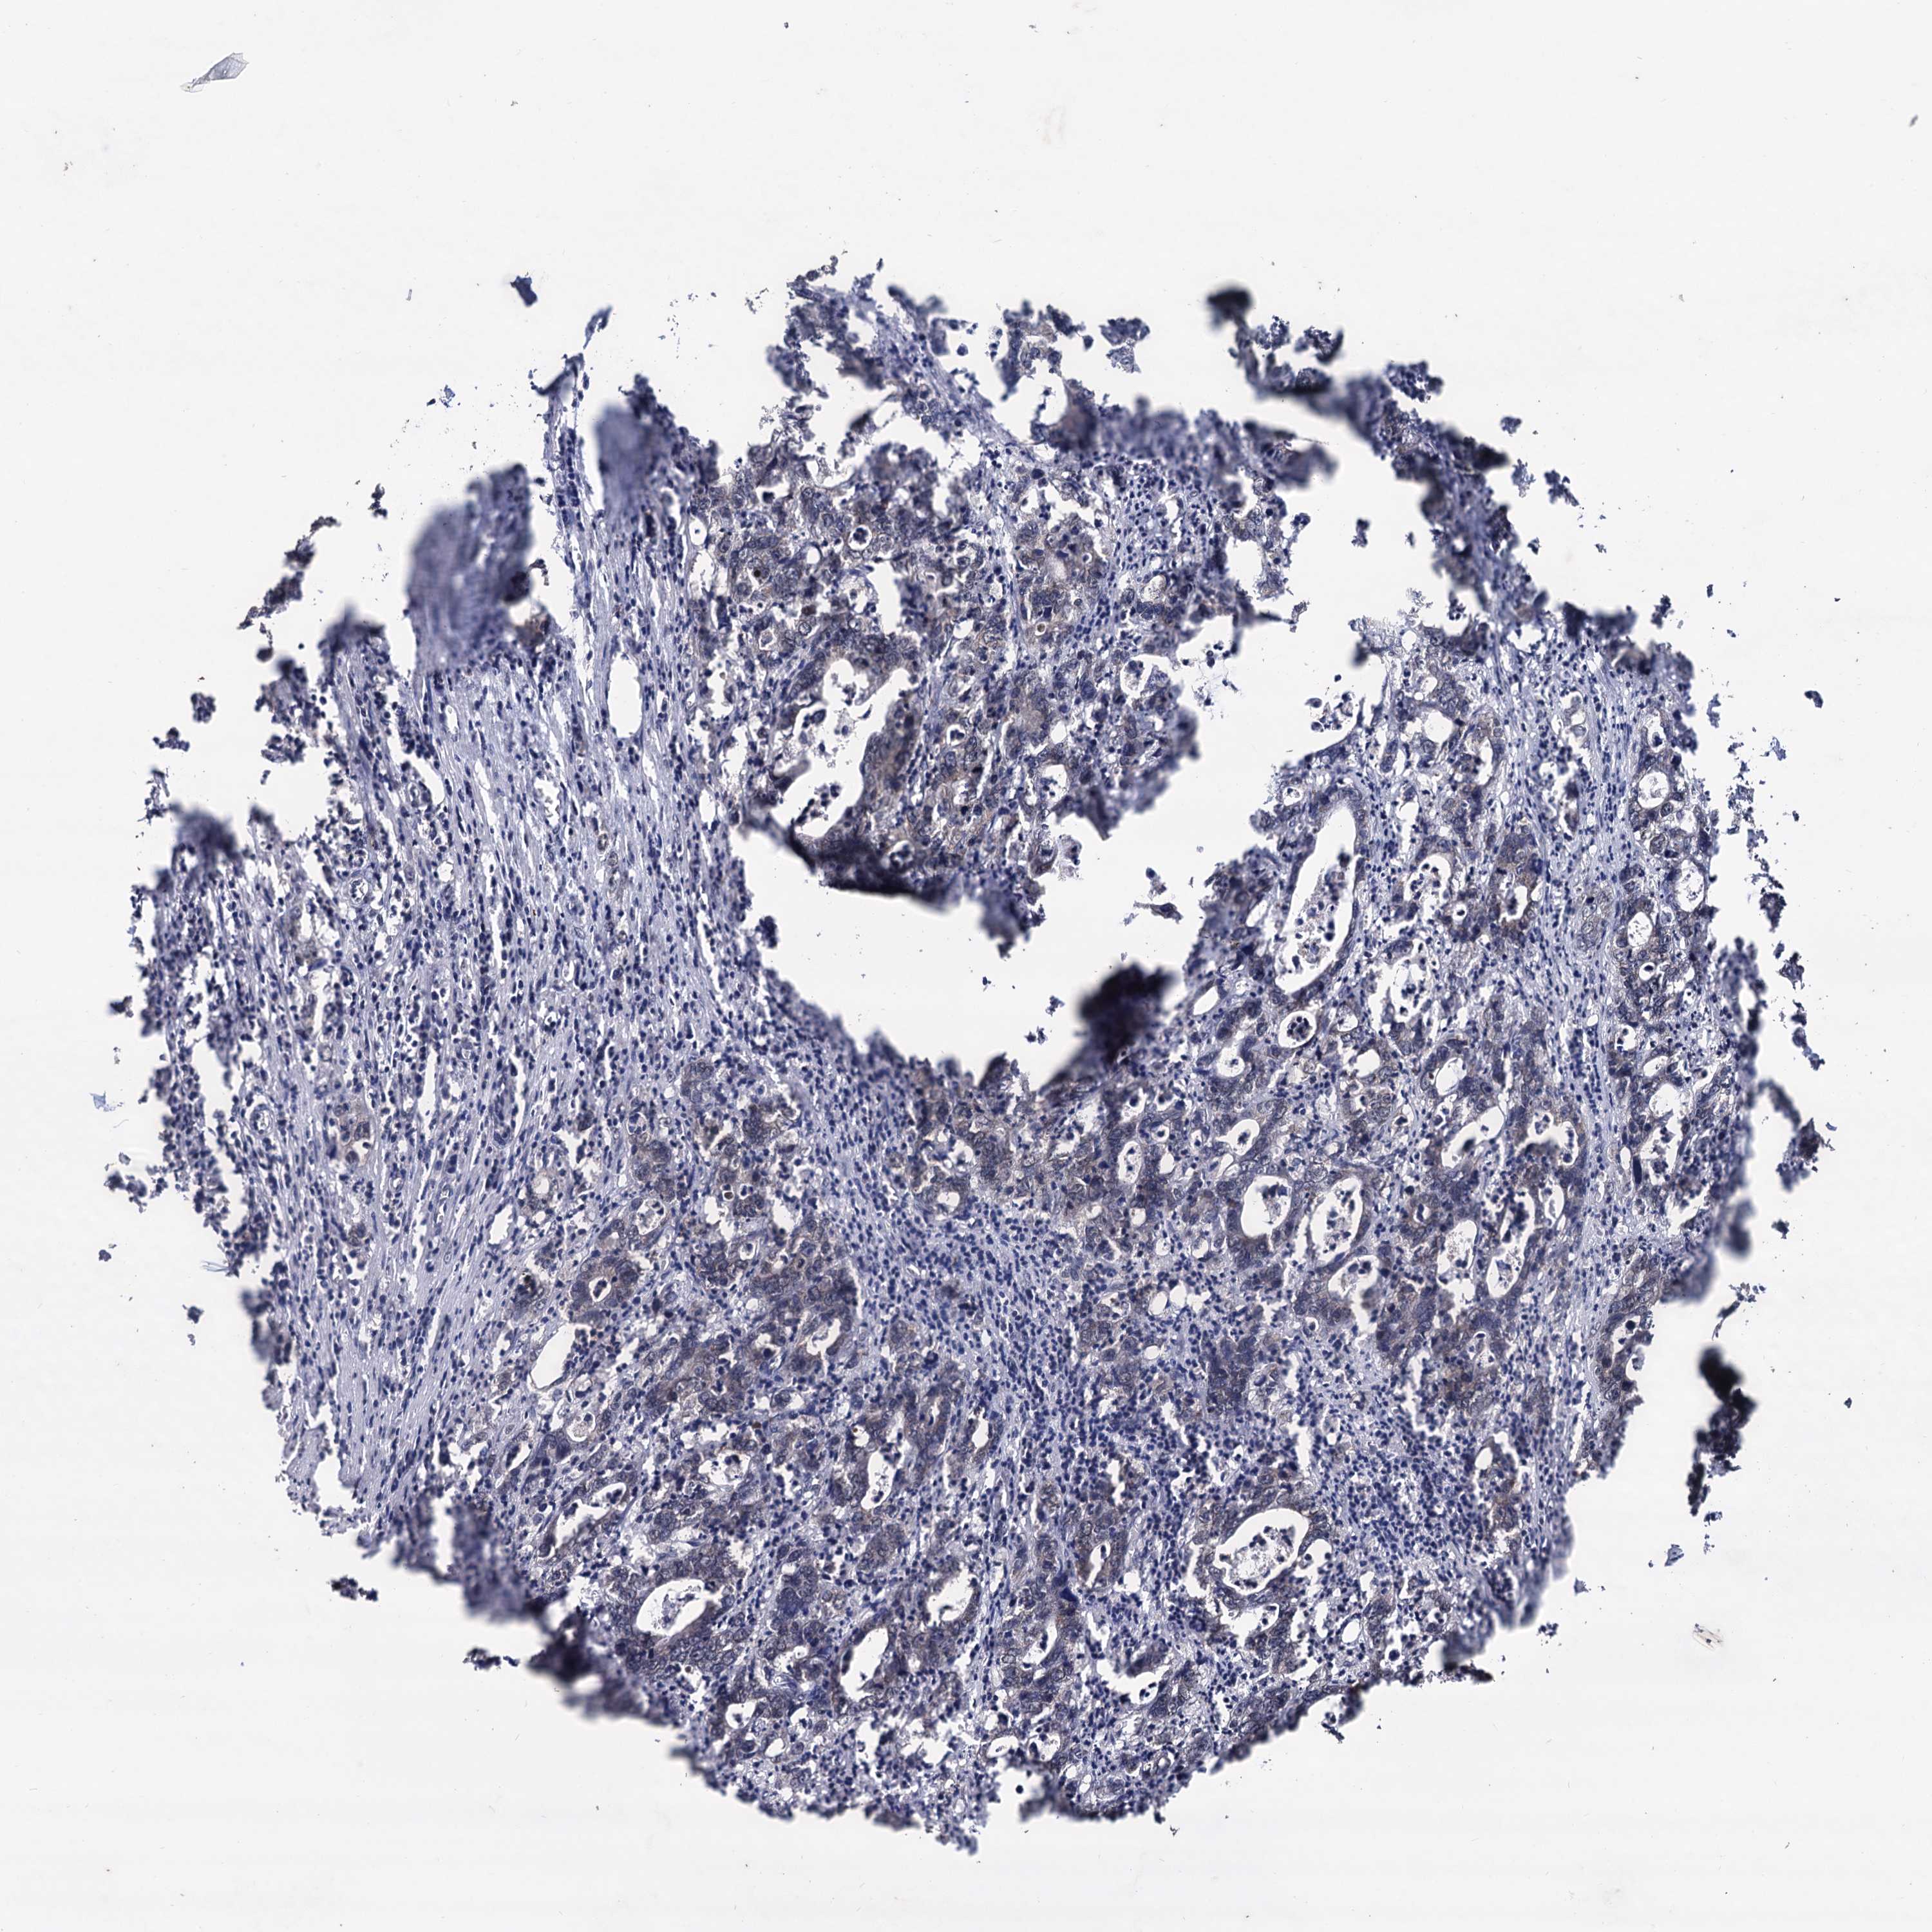

CANCER COLORECTAL CANCER Show tissue menu

Colorectal cancer

Human cancer

Rectum adenocarcinoma